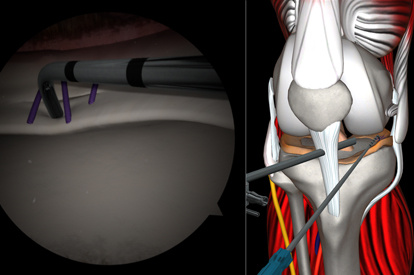

A Highly Effective and Validated Simulator for Core Arthroscopy Skills Acquisition

ARTHRO Mentor is an effective tool for arthroscopic surgery skills acquisition. With over 15 years of validation studies, it offers a line of simulated procedures, covering the 3 major joints (shoulder, knee, and hip) combining physical anatomical models with 3D images and dynamic haptic sensation, to allow users to learn key aspects of the procedures while providing tissue sensation.

Enjoy a safe and controlled environment for trainees to gain hands-on experience, with comprehensive and structured programs ideal for both novice and advanced learners and ready-to-use courses for independent training. With detailed feedback on the trainee’s performance, the ARTHRO Mentor simulator is a must-have tool for any arthroscopic surgical training program.

Features and Benefits

- Reduces training time and improves the learning curve

- A comprehensive didactic environment

- Self-learning structured curriculum in collaboration with KOLs

- Competence assessment based on performance metrics

- Adaptive tactile sensation on drilling, suturing, and shaving

- A library of modules with 80+ tasks, cases, and didactics

- Interchangeable knee, shoulder and hip models